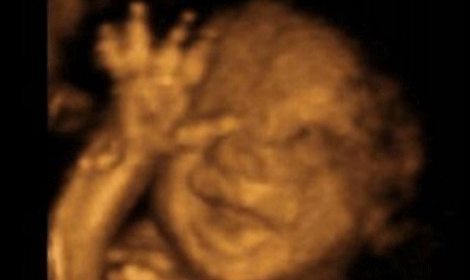

This very important conference provided a platform for parents, whose children had been diagnosed with terminal conditions, to talk about their individual experiences and to encourage better provision of perinatal hospice care.